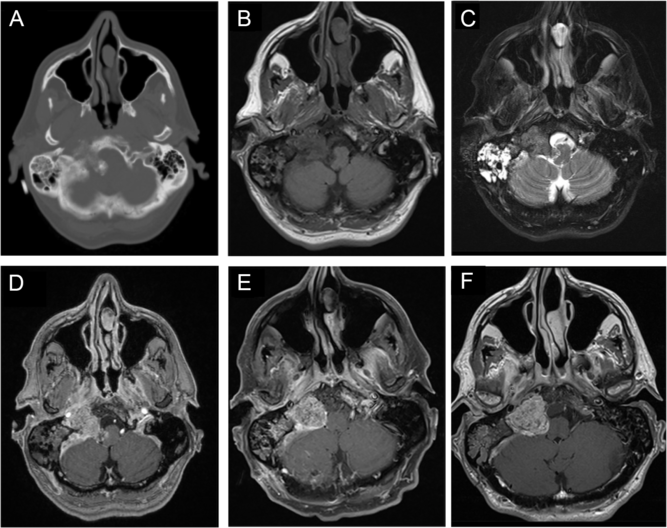

A previously healthy 57-year-old man with a past medical history significant for well-controlled asthma presented with 2 months of hoarseness, dysphagia, and gait imbalance. On physical exam, he had right-sided cranial nerves (CNs) IX, X, XI, XII palsies, as well as gait ataxia. Computed tomography (CT) of the head revealed a heavily calcified lesion within the right cerebellopontine angle (CPA), which seemed to originate from petrous temporal bone and condylar part of occipital bone with secondary involvement of right jugular foramen and hypoglossal canal, causing medulla compression (Figure 1A and B). On magnetic resonance imaging (MRI), this lesion was hypointense on T1-weighted images (T1WI; Figure 1B), isointense on T2-weighted images (T2WI; Figure 1C), and avidly enhancing with gadolinium (Figure 1C), without significant vasogenic edema. This was initially thought to be a meningioma, despite the absence of a dural tail. The portion centered in the right jugular foramen measured 3.5 × 2.1 × 2.0 cm (Figure 1B–D). Interestingly, CT and MRI also revealed diffuse right mastoid effusion; however, the patient had no subjective symptoms corresponding to this finding (Figure 1A–C).

Figure 1: Imaging of a right cerebellopontine angle (CPA) calcifying pseudoneoplasm of the neuraxis (CAPNON). Preoperative computed tomography (CT) of the head revealed a heavily calcified lesion within the right CPA involving right jugular foramen and hypoglossal canal, with medullary compression (A); on magnetic resonance imaging (MRI), this lesion was hypointense on T1-weighted images (B), isointense on T2-weighted images (C), and avidly enhancing with contrast (D), not associated with significant vasogenic edema. Postoperative MRI demonstrated a CAPNON residual in the jugular foramen, along with improved mass effect on the medulla (E). A 15-month follow-up MRI revealed slight progression in the size of right jugular foramen CAPNON (F).

Operation

Postoperatively, the patient showed significant improvement in his ataxia, but his cranial neuropathies persisted. At 15-months postoperatively, there was radiographic progression of the disease, with the residual lesion measuring 3.2 × 2.5 × 2.1 cm around the right jugular foramen (Figure 1G). However, the patient remained independent and well clinically.